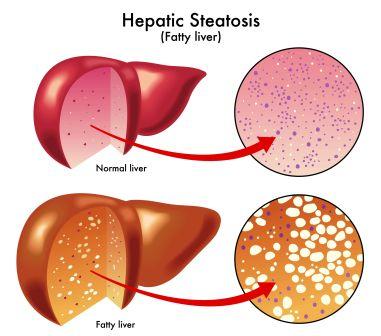

The tricky thing about fat is that, it can accumulate underneath the skin (to cause obesity) and also in some organs. Liver is one such organ wherein excessive fat accumulation can lead to a condition called Fatty liver disease or Steatosis.

Some amount of fat is normally present in the liver. But when the quantity of accumulated fat increases so as to contribute to more than 5-10% of its weight, the condition is known as Fatty Liver Disease.

It is a condition in which the liver cells accumulate abnormally increased amounts of fat. Excessive consumption of alcohol is a very common cause of Fatty Liver.

It is a reversible condition wherein large vacuoles of triglyceride fat accumulate in liver cells via a process of steatosis (abnormal retention of lipids within the cell).

FLD is associated with other diseases that influence fat metabolism. When this process of fat metabolism is disrupted, the fat can accumulate in the liver in excessive amounts, thus resulting in fatty liver. Accumulation of fat may also be accompanied by a progressive inflammation of the liver (hepatitis) called steato-hepatitis.

What happens in Non alcoholic fatty liver disease?

NAFLD is a manifestation of abnormality of metabolism within the liver. Liver handles metabolism of fat. Liver makes and exports fat to other parts of the body. It also removes fat from the blood that has been released by other tissues in the body, ex. By fat cells or absorbed from the food we eat.

In NAFLD, the mechanism by which the Liver handles fat and its metabolism gets disturbed. Increased amounts of fat are removed from the blood and / or increased amounts of fat are produced by liver cells.

On the other hand not enough amount of fat is disposed of or exported out by the liver cells. Thus there is an imbalance between input and output of fat. There is imbalance between fat deposition (accumulation) and fat clearance. As a result excess fat accumulates in the liver.

Pathology of fatty liver

Fatty changes represent the accumulation of triglycerides (neutral fats) in the cytoplasm of liver cells.

- Initial changes: Hepatocytes present small fat vacuoles (liposomes) around the nucleus (micro-vesicular fatty change). Here liver cells are filled with multiple fat droplets.

- Late stages: Size of the vacuoles increases, nucleus is pushed to the periphery of the cell giving a characteristic ‘signet ring’ appearance (macro-vescicular fatty change). These vesicles are well delineated and optically empty because fats dissolve during tissue processing. Large vacuoles may coalesce and produce fatty cysts which are irreversible lesions.

- Macro-vescicular steatosis is the most common form. It is typically associated with alcohol, diabetes, obesity and corticosteroids.

- The diagnosis of steatosis is made when fat in the liver exceeds 5-10% by weight

- Hepatic steatosis is considered reversible and to some extent non-progressive if the underlying cause is reduced or removed